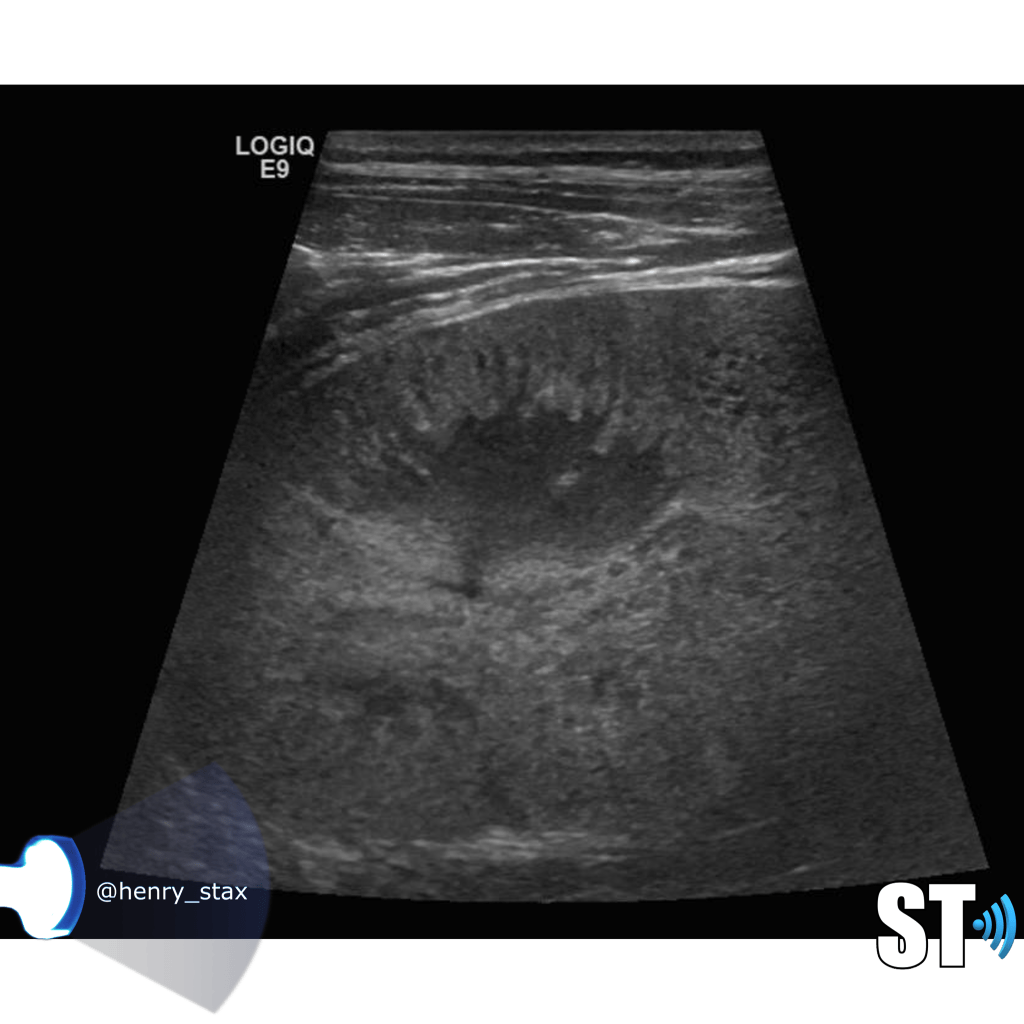

Renal Echogenicity

Another ultrasound sign of disease is echogenicity. Increased echogenicity is when the parenchymal echoes are greater than the liver. Usually the kidney is hypoechoic to almost isoechoic to the liver. Many different entities can cause increased echogenicity, that’s why when a radiologist reads an ultrasound with hyperechoic kidneys they usually attribute it to “medical renal disease”. A very hypoechoic kidney is also not normal, especially when it is focal as this could be due to infarction or infection.

The echogenicity of the kidney is just a single data point along with clinical and other laboratory findings a clinician can use in diagnosing renal disease.

For our purposes we need to tell whether the kidneys are hyperechoic or not, also is the corticomedullary (cmd) differentiation preserved or is it lost, this can give you clues as to the chronicity of renal parenchymal disease. If the cmd is easily seen it may suggest a more acute process, whereas chronic disease will usually show echogenic and atrophic kidney with little to no differentiation of the cortex to medulla

Glomerulonephritis

Glomerulonephritis is a collection of conditions that affect the glomerulus of the kidney as a result of immunological reactions involving the capillaries of the glomeruli. The kidney reacts to this immune response by

- Cellular proliferation

- Leukocytic infiltration

- Thickening of the glomerular basement membrane

- Hyalinization adn sclerosis

Patients typucally present with heamturia, azotemia, hypertension and red cell casts in the urine. Ultrasound findings are nonspecific you may see the range from normal kidneys to enlargement and increased echogenicity. With chronic glomerulonephritis you’ll typically see atrophic echogenic kidneys indistinguishable from kidneys in end stage renal failure.